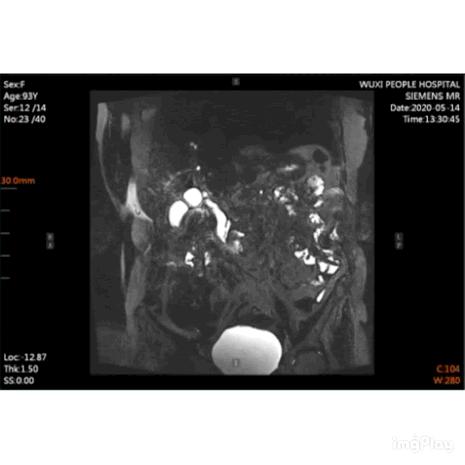

近日,无锡市人民医院消化内科成功为93岁高龄患者实施全麻下ERCP(经内镜逆行性胰胆管造影术)取石术,同时也打破了目前该科全麻下ERCP治疗患者中的最高年龄纪录。

93岁的赵阿婆半个月来饱受胆总管结石导致的急性胆管炎的折磨,持续的高热和腹痛令老人家萎靡不堪,保守抗感染治疗并没有缓解阿婆的症状。

在麻醉科的保驾护航下,消化内科ERCP团队凭借丰富的经验、熟练的操作技术,顺利完成了手术,成功取出多枚胆总管结石。术后按原定方案,患者进入重症监护室观察,于当晚顺利脱机拔管。阿婆术后未再腹痛、发热,现已平安出院。